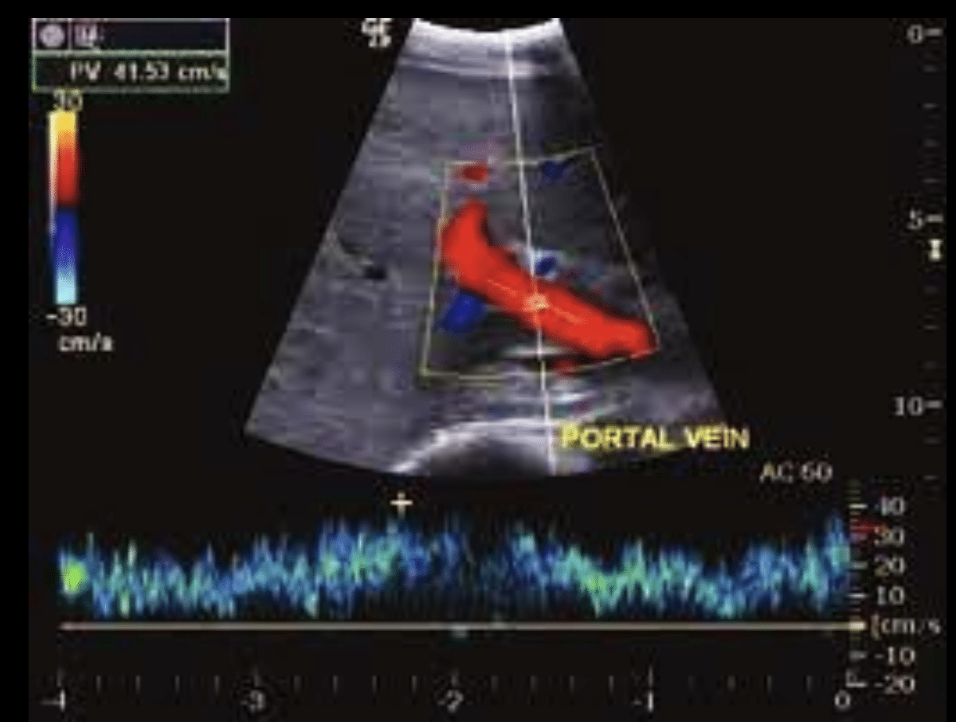

Doppler en vena porta